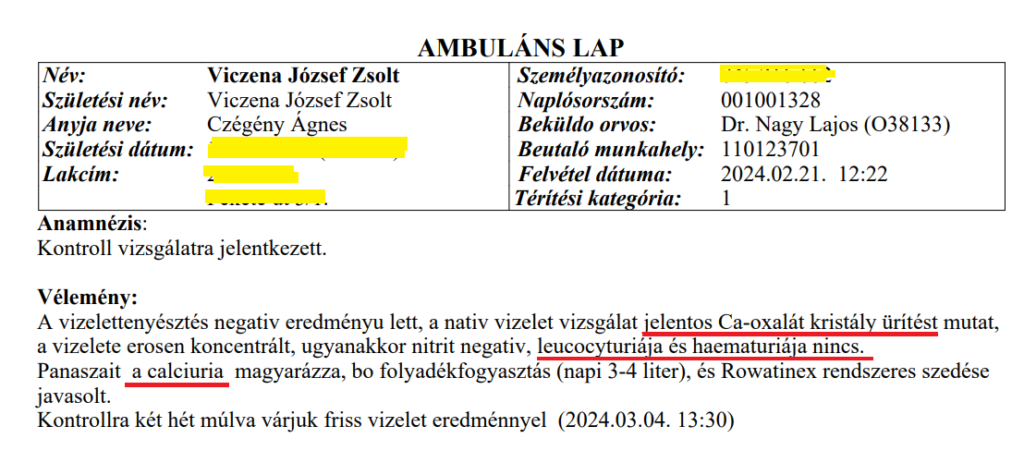

Dr. Nagy Lajos megnézte a leleteket, majd azt mondta: „Biztosan a gerince fáj… Szerintem a gerince fáj ott, ahol mutatja.” – mire a fiam megszólalt, hogy „A gerincem? Ezek a véseim, a veséim fájnak, súlyos vérvizelés van mellé”. Az orvos ezután nem írta le a 1000-szeres vérvizelés értékeket. A fiam a második (21-ei) alkalommal rékérdezett, hogy miért nem írta le a súlyos leleteket? Képzeljék el, Dr. Nagy Lajos azt mondta, hogy „Azért, mert nincs jelentőségük!” Hihetetlen volt! Ezerszeres vérvizelés értékeknek és Cola-színű vizeletnek nincs jelentősége extrém vesefájdalom társtüneteiként. Ezután kiválasztotta a 2 súlyos lelet mellett készült 3. leletet, ami épp nem tartalmazott vért, lekukocita észterázt, fehérjét, „csak” magas 130 kristályt/látótér és így kiállíthatott egy olyan leletet, hogy Zsoltnak se vérvizelése, se leukocyturiája nincs, így nincs akut, azonnali beavatkozást igénylő állapota se! – Az okot ráfogta a kristályürítésre, és Zsolt ezzel lett magára hagyva ismét.

Ennek ellenére szörnyű állapotában Február 21-én Zsolt ismét megkereste Nagy Lajost, aki rákérdezett , hogy megvan-e az általunk magán úton készíttetett vizelettenyésztés eredménye. A fiam közölte: „Hiszen Ön tudja, mert belépett az EESZT-mbe és látom, hogy ott van a lelet a kezében.” Ekkor én megjegyeztem, hogy „a fiam EESZT-je zárolt, csak a háziorvosa léphet be, tehát Ön belépett a fiam EESZT-jébe, ami az Digitális Önrendelkezés megsértése miatt teljesen törvénysértő volt.” Az orvos elvörösödött. Felírt egy saját beutalót mezei vizeletvizsgálatra, és távoztunk.